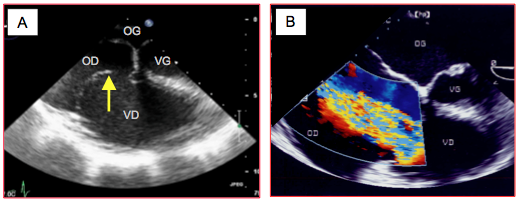

Figure 27.204 : Images échocardiographiques de tamponnade traumatique. A: épanchement liquidien circonférentiel. Ep : épanchement. B: épanchement hémorragique avec un caillot (flèche) lors d’une lésion traumatique de la paroi libre du VD.

- Insuffisance tricuspidienne (IT): rupture de cordage ou déchirure de feuillet, souvent découverte ultérieurement. Elle ne réclame pas d'intervention en urgence si elle est isolée car elle est bien tolérée, mais une reconstruction secondaire par plastie et anneau prosthétique est nécessaire si l’IT est de degré > modérée afin de protéger le VD de la dilatation (Figure 27.206) (voir Chapitre 11 Insuffisance tricuspidienne) [12].

Figure 27.206 : Insuffisance tricuspidienne massive par rupture traumatique de cordage de la valve, avec dilatation de l'OD et du VD. A : bascule du feuillet antérieur (flèche) entraîné par la rupture de cordage. B : insuffisance tricuspidienne massive au Doppler couleur (IT).